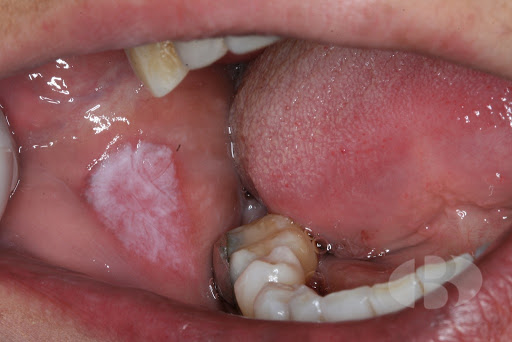

Todos sabemos que durante estos días, los mayores de la casa han estado encerrados para evitar los efectos del Coronavirus. Razón por la que muchas de las lesiones que habitualmente tienen en sus bocas pueden haber aumentado o modificado su importancia. Por esa razón, creemos que ante la presencia de una úlcera, un sangrado inexplicable, dolor o una lesión nueva, deben acudir a la clínica Sciaini lo antes posible.Si por razones de edad o movilidad, no pudiese desplazarse te rogamos realices a tu familiar una foto con el móvil, para obtener una primera impresión diagnóstica y envíala a nuestro mail. Posteriormente nosotros nos desplazaremos hasta su domicilio para comprobar su estado y así evitar desplazamientos innecesarios.La salud de los más mayores sigue siendo para nosotros muy importante.